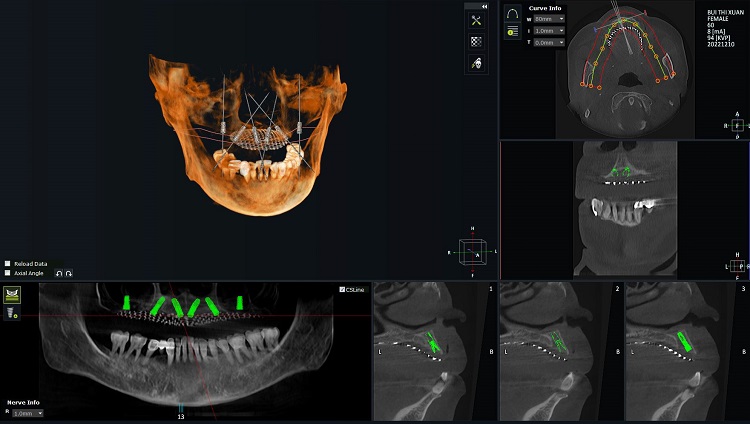

Các bác sĩ lên kế hoạch điều trị cho cô Xuân bằng phần mềm kỹ thuật số hiện đại

Sau khi thăm khám cho cô Xuân, Bác sĩ Nguyễn Ngọc Bảo cho biết cô Xuân đang gặp một số tình trạng như:

- Mất toàn bộ răng hàm trên.

- Xương hàm tiêu lép nhiều do mất răng lâu năm.

Với những đánh giá tổng quan ban đầu kết hợp với nhu cầu khôi phục hàm răng thẩm mỹ, bền đẹp, dễ dàng bảo hành, sửa chữa, đội ngũ y bác sĩ tại Nha khoa Lạc Việt Intech đã đưa ra phương án điều trị như sau:

- Cấy ghép implant All on 6 toàn hàm trên.

- Ghép xương ở các vị trí bị thiếu xương.

- Phục hình 14 răng sứ.

Quá trình trồng răng implant của cô Bùi Thị Xuân có sự kết hợp của công nghệ Safe-tech. Đây là công nghệ độc quyền đang được áp dụng tại Nha khoa Lạc Việt Intech hỗ trợ bác sĩ lên kế hoạch điều trị chính xác, cấy ghép implant an toàn, tránh các dây thần kinh, giảm thiểu đau nhức cho khách hàng.